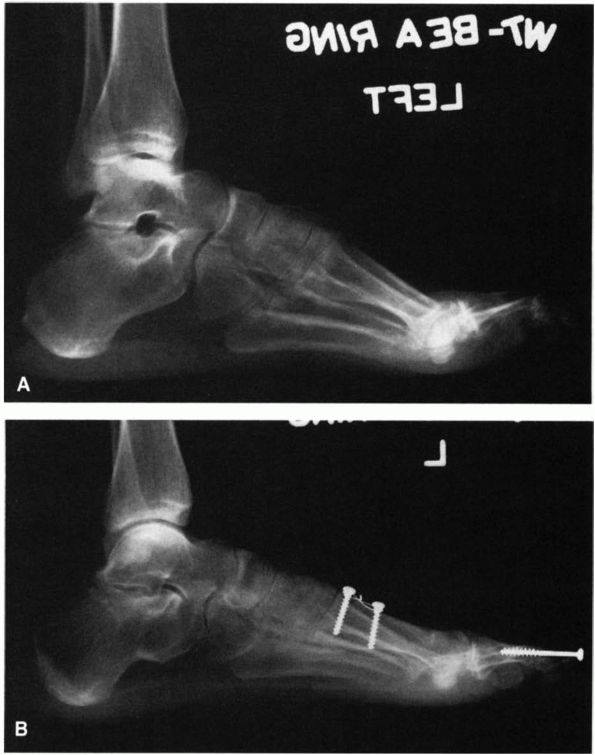

![]() |

|

FIGURE 21-25. Operative correction of a cavus foot. (A) Preoperative deformity demonstrating the increased dorsiflexion pitch of the calcaneus and mild equinus of the forefoot. (B)

Postoperative radiograph after a calcaneal osteotomy permitting dorsiflexion of the proximal fragment, dorsiflexion osteotomy of the first metatarsal, release of the plantar fascia, and fusion of the interphalangeal joint of the great toe. The longitudinal arch has been lengthened as a result of this procedure. (Mann RA, Coughlin MJ. The Video Textbook of Foot and Ankle Surgery. St Louis: Medical Video Productions, 1991) |